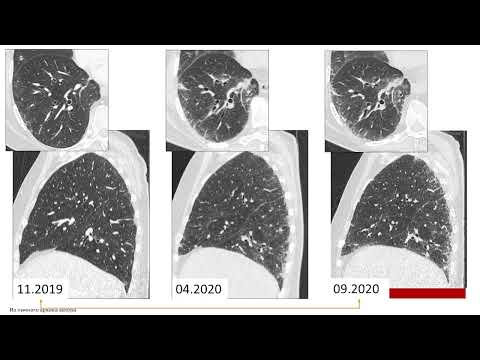

Современные подходы к лечению идиопатического легочного фиброза. Клиническая практика

Современные подходы к лечению идиопатического легочного фиброза. Клиническая практика. Мержоева Замира Магомедовна, к.м.н., ассистент кафедры пульмонологии ФГАОУ ВО Первый МГМУ им. И.М. Сеченова Минздрава России «Сеченовский Университет». АНО Научное медицинское общество «Медицинская практика».